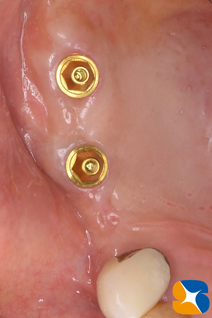

手術から3ヶ月後の様子です。

手術から4ヶ月後の様子です。